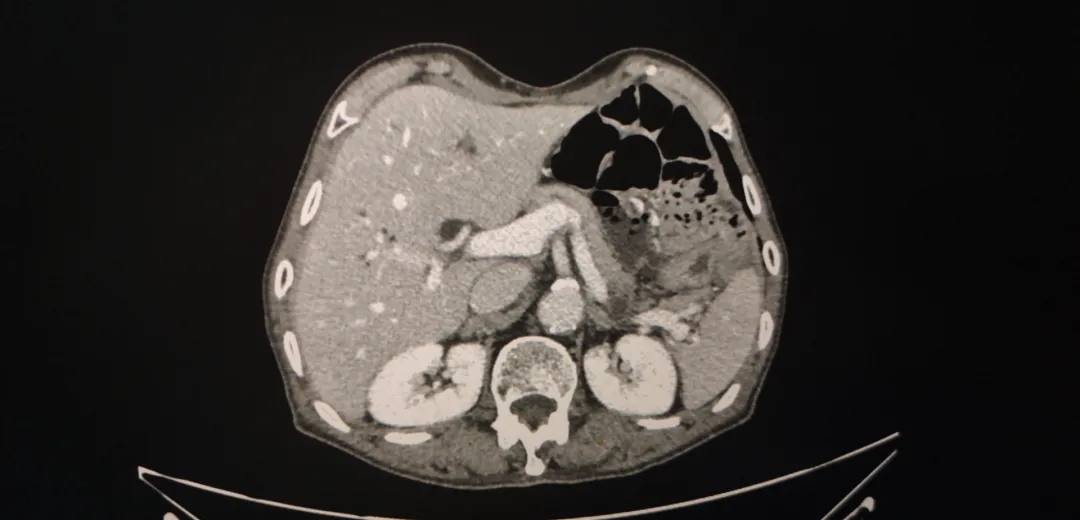

2019-11 腹盆CT

上腹+盆腔增强CT( 2019-11-25 ):

与2019.4.22腹盆CT片比较:肝内胆管扩张较前明显,请结合临床。